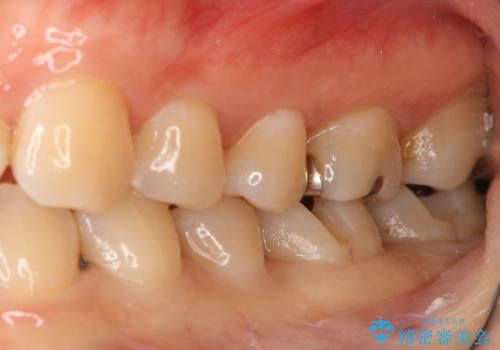

- 左下奥歯のメタルインレーを白くしたいと希望された患者様です。

形態、切削量などを考慮し、セラミックインレーにて治療を行いました。

メタルインレー、う蝕除去後にCRにて裏層した上で、形成・印象を行いました。